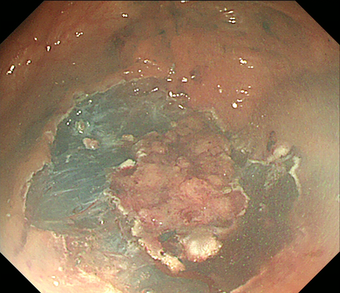

3)内視鏡的粘膜下層剥離術(ESD)

2cmを越える大きな腫瘍では、通常の内視鏡的ポリープ切除や粘膜切除術では一度に切除することが難しくなります。何度かに分割して切除すると再発率が高いため、内視鏡的粘膜下層剥離術(ESD)で腫瘍全体を一度に切除する方法を行います。ESDではヒアルロン酸溶液などを粘膜下に注入し病変を盛り上げてから、ナイフで少しずつ病変を削り取って切除します。現在のところ大腸がんに対するESD は高度先進医療実施施設でのみ実施が可能です。大きな潰瘍ができるため出血や穿孔の危険性が高くなるため、通常1週間くらいの入院が必要です。

図 大腸がん